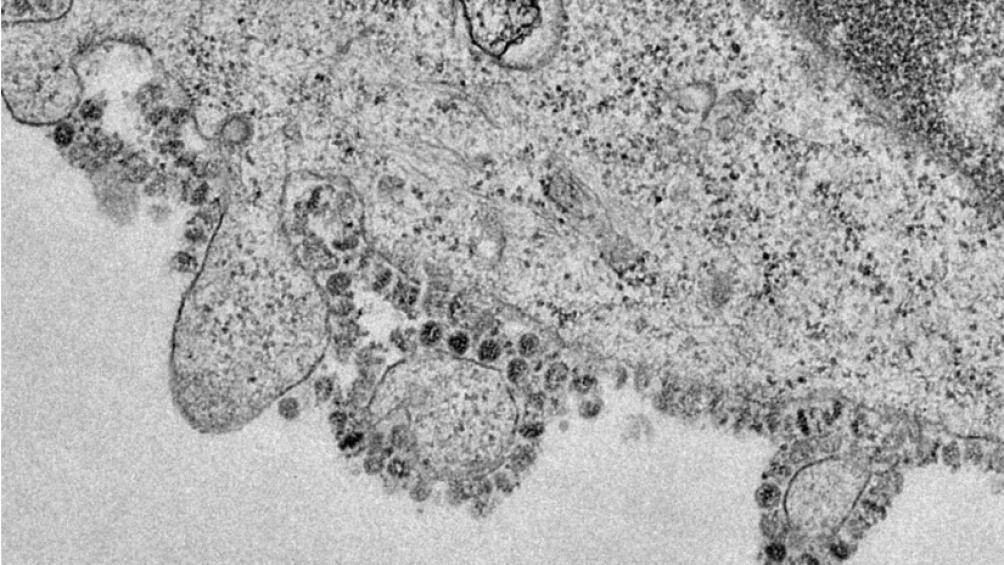

Trong quá khứ, Quỹ Gates chính là nguồn lực tài chính gây dựng nên Liên minh Sáng kiến Chuẩn bị cho Đại dịch (CEPI), được thành lập sau khi đại dịch Ebola bùng phát tại Châu Phi hồi năm 2014. Hiện tại, CEPI cũng là đơn vị đang nghiên cứu phát triển vaccine cho virus Corona biến thể mới xuất hiện ở Vũ Hán, Trung Quốc.

Trong bối cảnh virus cúm chủng corona tiếp tục lan ra, Quỹ Bill và Melinda Gates tuyên bố sẽ đóng góp 10 triệu USD cho cuộc chiến chống dịch bệnh. Trong số này, 5 triệu USD sẽ được dùng để giúp đỡ Trung Quốc và 5 triệu USD còn lại sẽ được đổ về Châu Phi, cụ thể là Trung tâm Kiểm soát và Ngăn ngừa Dịch bệnh, nhằm chuẩn bị cho những đợt bùng phát dịch có thể có trong tương lai.

Trong thông cáo báo chí do Quỹ Bill và Melinda Gates gửi đi có ghi rõ rằng số tiền sẽ được dùng vào các quỹ khẩn cấp và trợ giúp kỹ thuật giúp đỡ những người trực chiến ở tiền tuyến tại Trung Quốc và Châu Phi, thúc đẩy nỗ lực của họ để ngăn chặn việc 2019-nCoV lan ra toàn cầu.